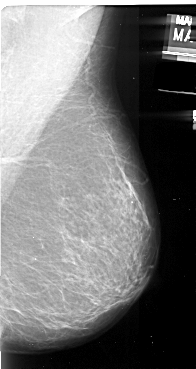

A_1094_1.RIGHT_MLO

RIGHT_CC LINES 5296 PIXELS_PER_LINE 2806 BITS_PER_PIXEL 16 RESOLUTION 42 NON_OVERLAY

RIGHT_MLO LINES 5521 PIXELS_PER_LINE 2926 BITS_PER_PIXEL 16 RESOLUTION 42 NON_OVERLAY